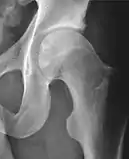

Radiograph of a pincer type impingement.

Projectional radiography ("X-ray")is often considered first line for FAI.[11] Anterior-posterior pelvis and a lateral image of the hip in question should be attained.[11] A 45-degree Dunn view is also recommended.[11][19]